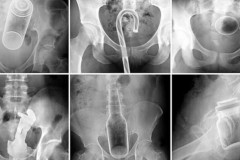

10 տարօրինակ առարկա, որ հայտնվել են մարդկանց օրգանիզմում. հետաքրքիրն այն է, թե ի...